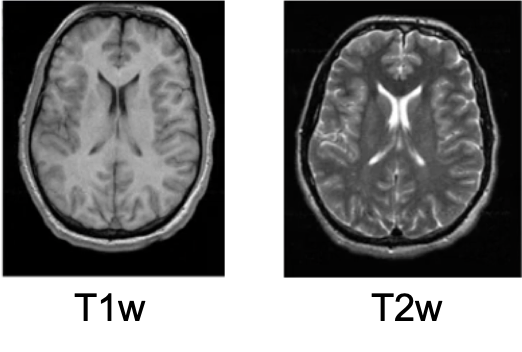

在这两张图片上,很容易看出它们没有对齐,左边相对右边倾斜,虽然我们人类视觉系统还是能把对应的解剖关系连系在一起,但是我们使用计算机分析时确不能够

现在讨论一个场景:我们有两个不同的图像,它们来自同一个患者,其中一个是t1加权图像,一个是t2加权图像,因此我们需要考虑如何设置配准参数

我们要使这两个序列的图像对齐,有两种方法。一个是把T2w配到T1w上(T1w作为参考图像,T2w作为输入图像);另一种就是反过来,T1w配到T2w.

一般原则是,把分辨率好的,对比度好的作为参考图像。

这个情况下,来自同一次检查的不同序列,可以视为一个刚体(rigid body), 因为病人只能够旋转和平移头部,这是几何上的唯一区别。

因此,我们可以选择刚体变换,6个自由度;代价函数可以选择 相关比或者互信息, 二者都适用于不同模态之间的转换。